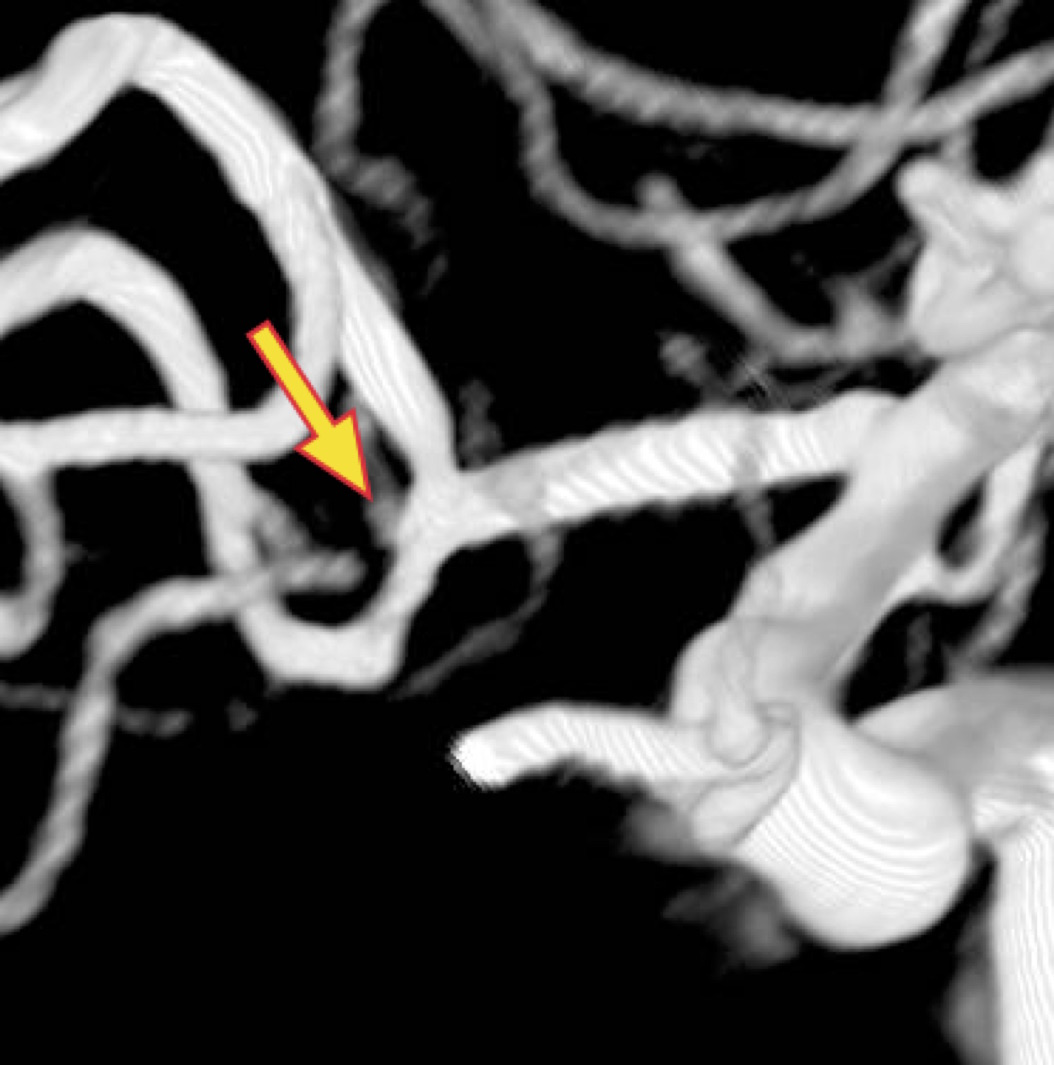

<3DCTA:コイル塞栓前>

矢印は動脈瘤

<3DCTA:コイル塞栓後>

矢印は動脈瘤の消失を示す